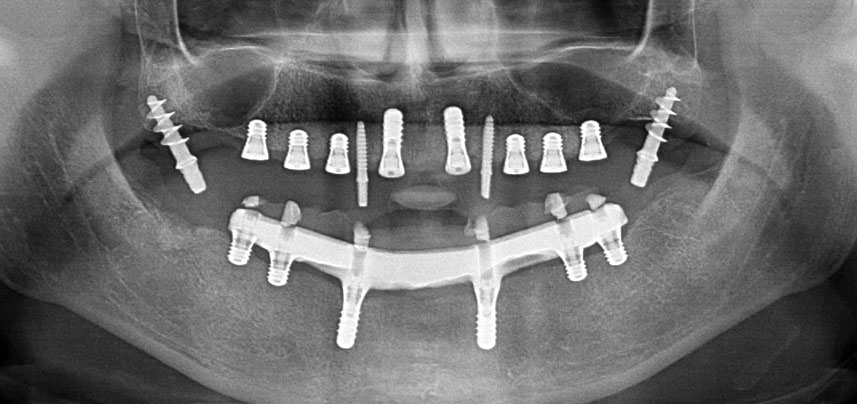

Chez les patients édentés, les prothèses fixes sur implants améliorent la mastication et la qualité de vie. Du fait d’une résorption et d’une hyper-pneumatisation des sinus, un patient présentait une faible hauteur osseuse dans la zone maxillaire postérieure. Les sites implantaires ont été préparés à l’aide d’un dispositif piézoélectrique et d’une nouvelle gamme d’inserts dédiés. Deux implants de 10mm et six implants de 4mm ont été posés pour retenir une prothèse CAD/CAM fixe soutenue par une barre.

Trois ans après, le moment était venu pour elle de se doter d’une prothèse maxillaire du même type. Sur la base de la planification CBCT, l’élévation sinusale a été évitée grâce à la pose d'implants courts, et un gabarit chirurgical a été utilisé pour transférer les positions planifiées sur la crête alvéolaire (Figures 1 et 2).

Compte tenu de la dureté relative de l’os (D2) à cet endroit, les sites recevant des implants de 10mm de long aux régions 11 et 21 ont été finalisés à l'aide d’une fraise de 4mm de diamètre, associée à un contre-angle chirurgical W&H WS-75 L, au moteur d'implantologie Implantmed de W&H ainsi qu’au module Osstell ISQ de W&H. En revanche, en raison de leur structure osseuse molle, les sites postérieurs ont été préparés en vue de l’obtention d’un diamètre final de 3mm à l'aide de l’insert Piezomed I3P. Les implants ont enfin été posés par voie transgingivale (Flap Less) pour obtenir l’ostéointégration dans un délai de trois mois (Figures 6-10). L'appareil existant a été maintenu sur quatre implants provisoires (Fig. 8).